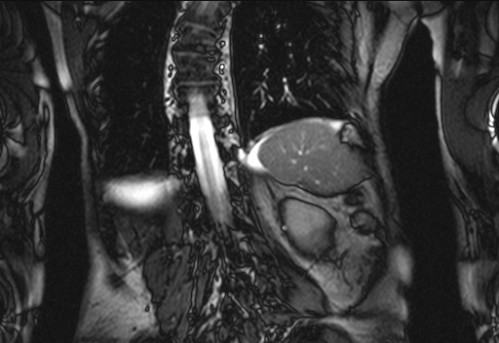

Auffälliges Abdomen bei der Vorsorgeuntersuchung einer älteren Dame

ICD: C64

68 Jahre alte Frau. Sie geht zur Darmspiegelung im Rahmen ihrer Krebsvorsorgeuntersuchung. Der Internist bemerkt bei der ergänzenden sonografischen Untersuchung des Abdomens einen auffälligen Befund.